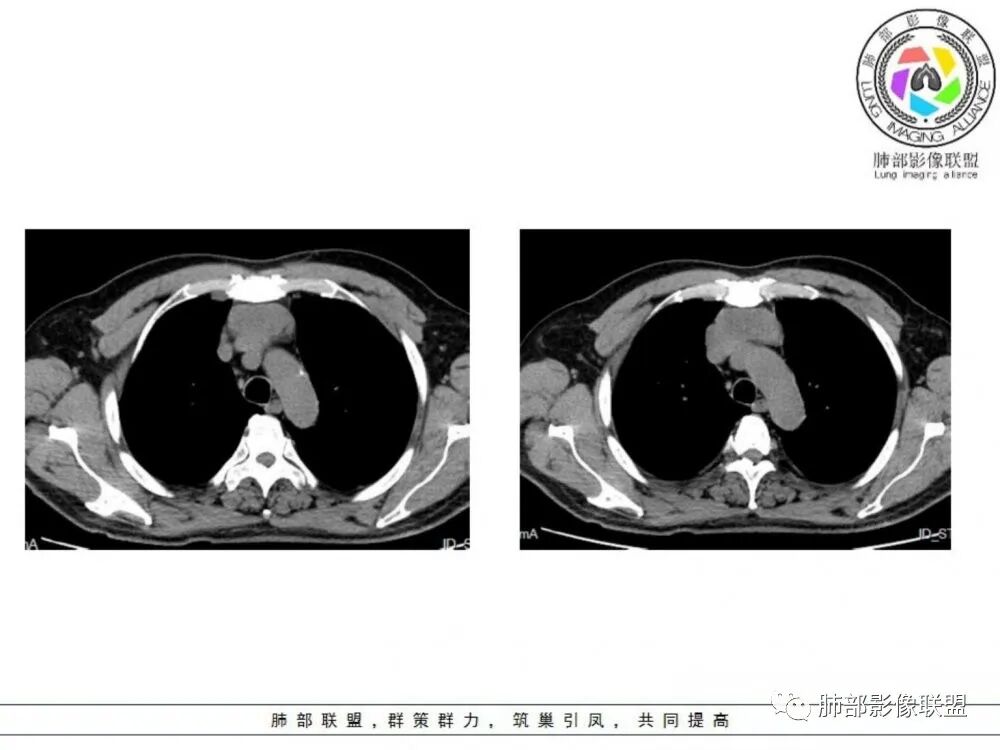

临床,老年男性,病史一月。1 定位,骑跨大血管,大部分位于胸腺区域内,周边部分胸腺脂肪有混浑浊,起源于胸腺区的组织应该没有问题。2 定性 。恶性征像,分叶,大血管侵润,pet高代谢,左侧庄层胸膜增厚(类似脑膜瘤的脑膜尾征,良性表现?)。良性征像,病灶均匀,无明确坏死?综合恶性征像多些,考虑恶性可能大。病灶分两部分,部分层面似有明确分割,两个性质的病灶长一块,还是,一个病灶两种不同成分?一个病灶伴均匀坏死?CT值41hu,坏死好像高了点,一个病灶,相同成分,只是血管分布不同,增强是持续流入型强化。纤维类?编不下去了,岔路太多,祭出法宝按概率蒙吧:侵袭性胸腺瘤>神经纤维瘤>乏血供CD

前纵隔胸腺区分叶状软组织肿块影,轻度不均匀强化,中心可见坏死,边缘不清,病灶与邻近心包见条索影,上腔静脉受侵,上纵隔多发小淋巴结,考虑胸腺鳞癌可能。

前纵隔不规则肿块,边缘彭隆,周围脂肪间隙消失,主动脉受压,上腔静脉部分受侵,平扫密度尚均匀,增强后不均匀强化,强化较轻,考虑胸腺癌,鉴别神经鞘瘤(强化偏弱了)

男性患者,65岁,前胸后背疼痛一个月。胸部影像:前上纵隔分叶状的软组织肿块,形态不规则,包绕大血管生长趋势,与周围分界不清,密度较均匀,呈多结节融合,肿块周围可见肿大淋巴结,内乳动脉旁淋巴结大,上腔受累,肿物内可见低密度区,增强扫描周围轻度强化。考虑:恶性病变,淋巴瘤?胸腺神经内分泌肿瘤?鉴别胸腺瘤

中老年男性,前纵隔占位,基本居中,向两侧生长;边缘膨隆分叶,部分边界不清,增强不均匀轻中度强化,坏死区边界不清;周围多发增大淋巴结,考虑恶性。主要在胸腺癌、胸腺瘤、淋巴瘤之间鉴别。病灶偏软,有钻缝样生长,这些征象偏向于淋巴瘤。但此例老年患者,病灶内有点状钙化,缺乏结节堆砌感,倾向胸腺癌诊断。